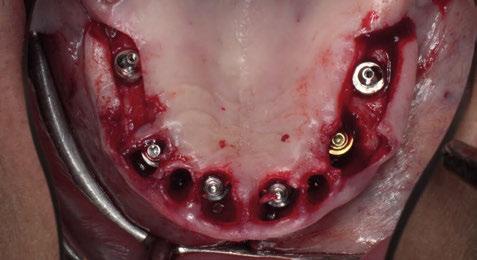

Figura 1. El sistema Di2gitalArch.